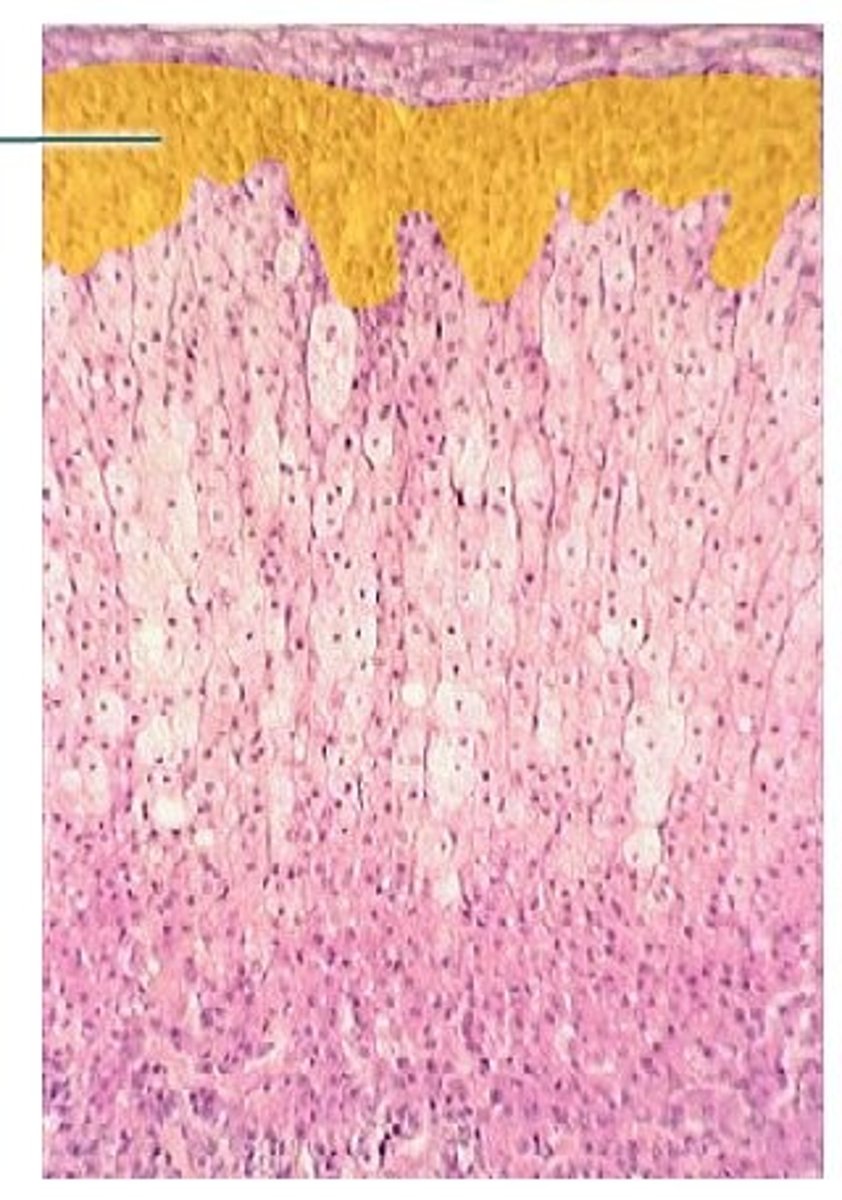

zona glomerulosa

What zone of the adrenal cortex:

-located immediately inside the capsule

-composed of columnar cells in spherical/ovoid groups

-makes mineralcorticoids (aldosterone)

zona fasciculata

-middle layer

-composed of basophilic cells in parallel columns sepaarated by capillaries

-makes glucocorticoiods (cortisol)

-affects carbohydrate metabolism by stimulating gluconeogenesis and glycogen synthesis; suppresses immune function, controlled by ACTH

zona reticularis

-innermost layer of adrenal cortex

-composed of branching/anastomosing cords of darker staining small cells

-makes weak androgens

-stimulated by ACTH